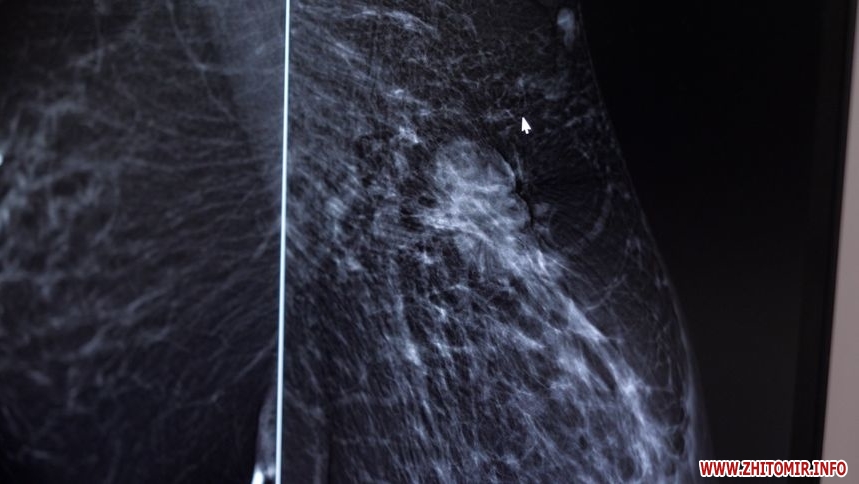

Щодня у приміщенні житомирської поліклініки №1 проводять близько 25 досліджень за допомогою цифрової мамологічної системи. Скільки обстежень молочних залоз повели у 2024 році та скільки захворювань виявили, 8 січня дізнавалися журналісти Житомир.info.

«Апарат за сприянням мерії з'явився в грудні 2020 року. Це один із найсучасніших, італійський апарат, який надає можливість виявити пухлини на ранніх стадіях, тобто 1-2 мм. Його вартість 9 млн грн. За 2024 рік проведено – 2 762 обстежень, з них було виявлено 62 підозри, це означає, що після обстеження біопсії, з ймовірністю 90% у жінок буде рак молочної залози. В області до 400 жінок хворіють на рак грудної залози, це від першої до четвертої стадії», – розповідає лікар хірург-онколог міського мамологічного центру КП «Лікарня №1» Житомирської міської ради Ярослав Сущенко.

«Зазвичай обстеження дівчатам потрібно починати з 18 років. Саме це УЗД молочних залоз проводиться до 40 років. З 40 років до УЗД додається мамограма раз у 2 роки. Якщо на обстеженні УЗД до 40 років лікар виявляє щось підозріле, то може направити для дообстеження на мамограму. А так, зазвичай, мамограма проводиться планово усім жінкам з 40 років. У нас є запис, тому що багато жінок проходять обстеження, але запис не такий великий, 1-2 тижні й можна потрапити. Якщо є якісь підозри, то ми входимо в положення пацієнта й намагаємося швидше прийняти, щоб зробити мамографію», – каже лікар хірург-онколог міського мамологічного центру КП «Лікарня №1» Житомирської міської ради